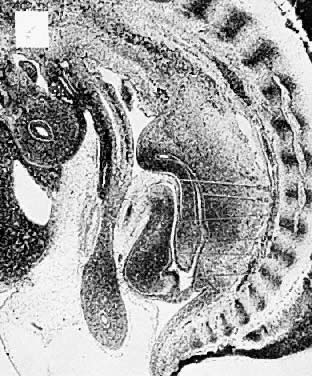

The hindgut (Fig. 6 and Fig. 7) plays an exceedingly important part in the development of the infraumbilicai abdominal wall, external genitalia, perineum, anus, and lower genitourinary tract. As early as 13 days after conception, the hindgut becomes active, and its importance and differentiation continue through the 12th week of gestation. A variety of malformations can occur, depending on the age of the embryo and whether agenesis, embryonic fissure, embryonic arrest, or duplication is the mechanism involved. The most damaging malformation is sympodia or absence of the entire hind end of the body. Such damage occurs early and results in destruction of portions of the lower extremities, perineum, and cloaca. Absence of the perineum leaves no genital, urinary, or anal orifices; lower urinary and müllerian tract derivatives are absent. Damage occurring later may result in exstrophy of the cloaca and, later still, exstrophy of the bladder. Exstrophy of the bladder may be incomplete or complete. Complete exstrophy is the most common type and is associated with wide separation of the pelvic bones, complete epispadias, and protrusion of the entire posterior bladder wall. The failure is that of midline fusion rather than absence of abdominal wall musculature. Ureteral duplications, uterine and vaginal duplications, and imperforate anus are frequently associated with exstrophy of the bladder. This occurs in approximately 1 of 40,000 births. Unless adequately treated, ascending pyelonephritis results in early death. The results of surgery are usually good, with fair life expectancy. A number of women have delivered living infants after operative repair of the defect. Prolapse of the uterus usually follows vaginal delivery.

Fig. 6. Diagrammatic sections of human embryos of approximately 2, 21/2, 4, and 5 weeks. Area of interest is circled. A indicates allantois; C, cloacal membrane; C1, cloaca. Ectoderm is shown by heavy black line; endoderm by beaded line; mesoderm by stippled area. Urorectal fold is indicated by asterisk in C and D. (From Spencer R: Exstrophia splanchnia [exstrophy of the cloaca]. Surgery 57:751, 1965.)

Fig. 7. Hindgut, cloaca, and allantois (After Moore KL: Developing Human. Philadelphia: Saunders, 1973.)